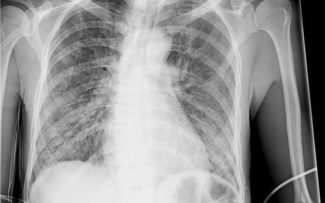

“A pneumonia da Covid-19 é muito diferente da comum. Ela evolui com fibrose pulmonar”.